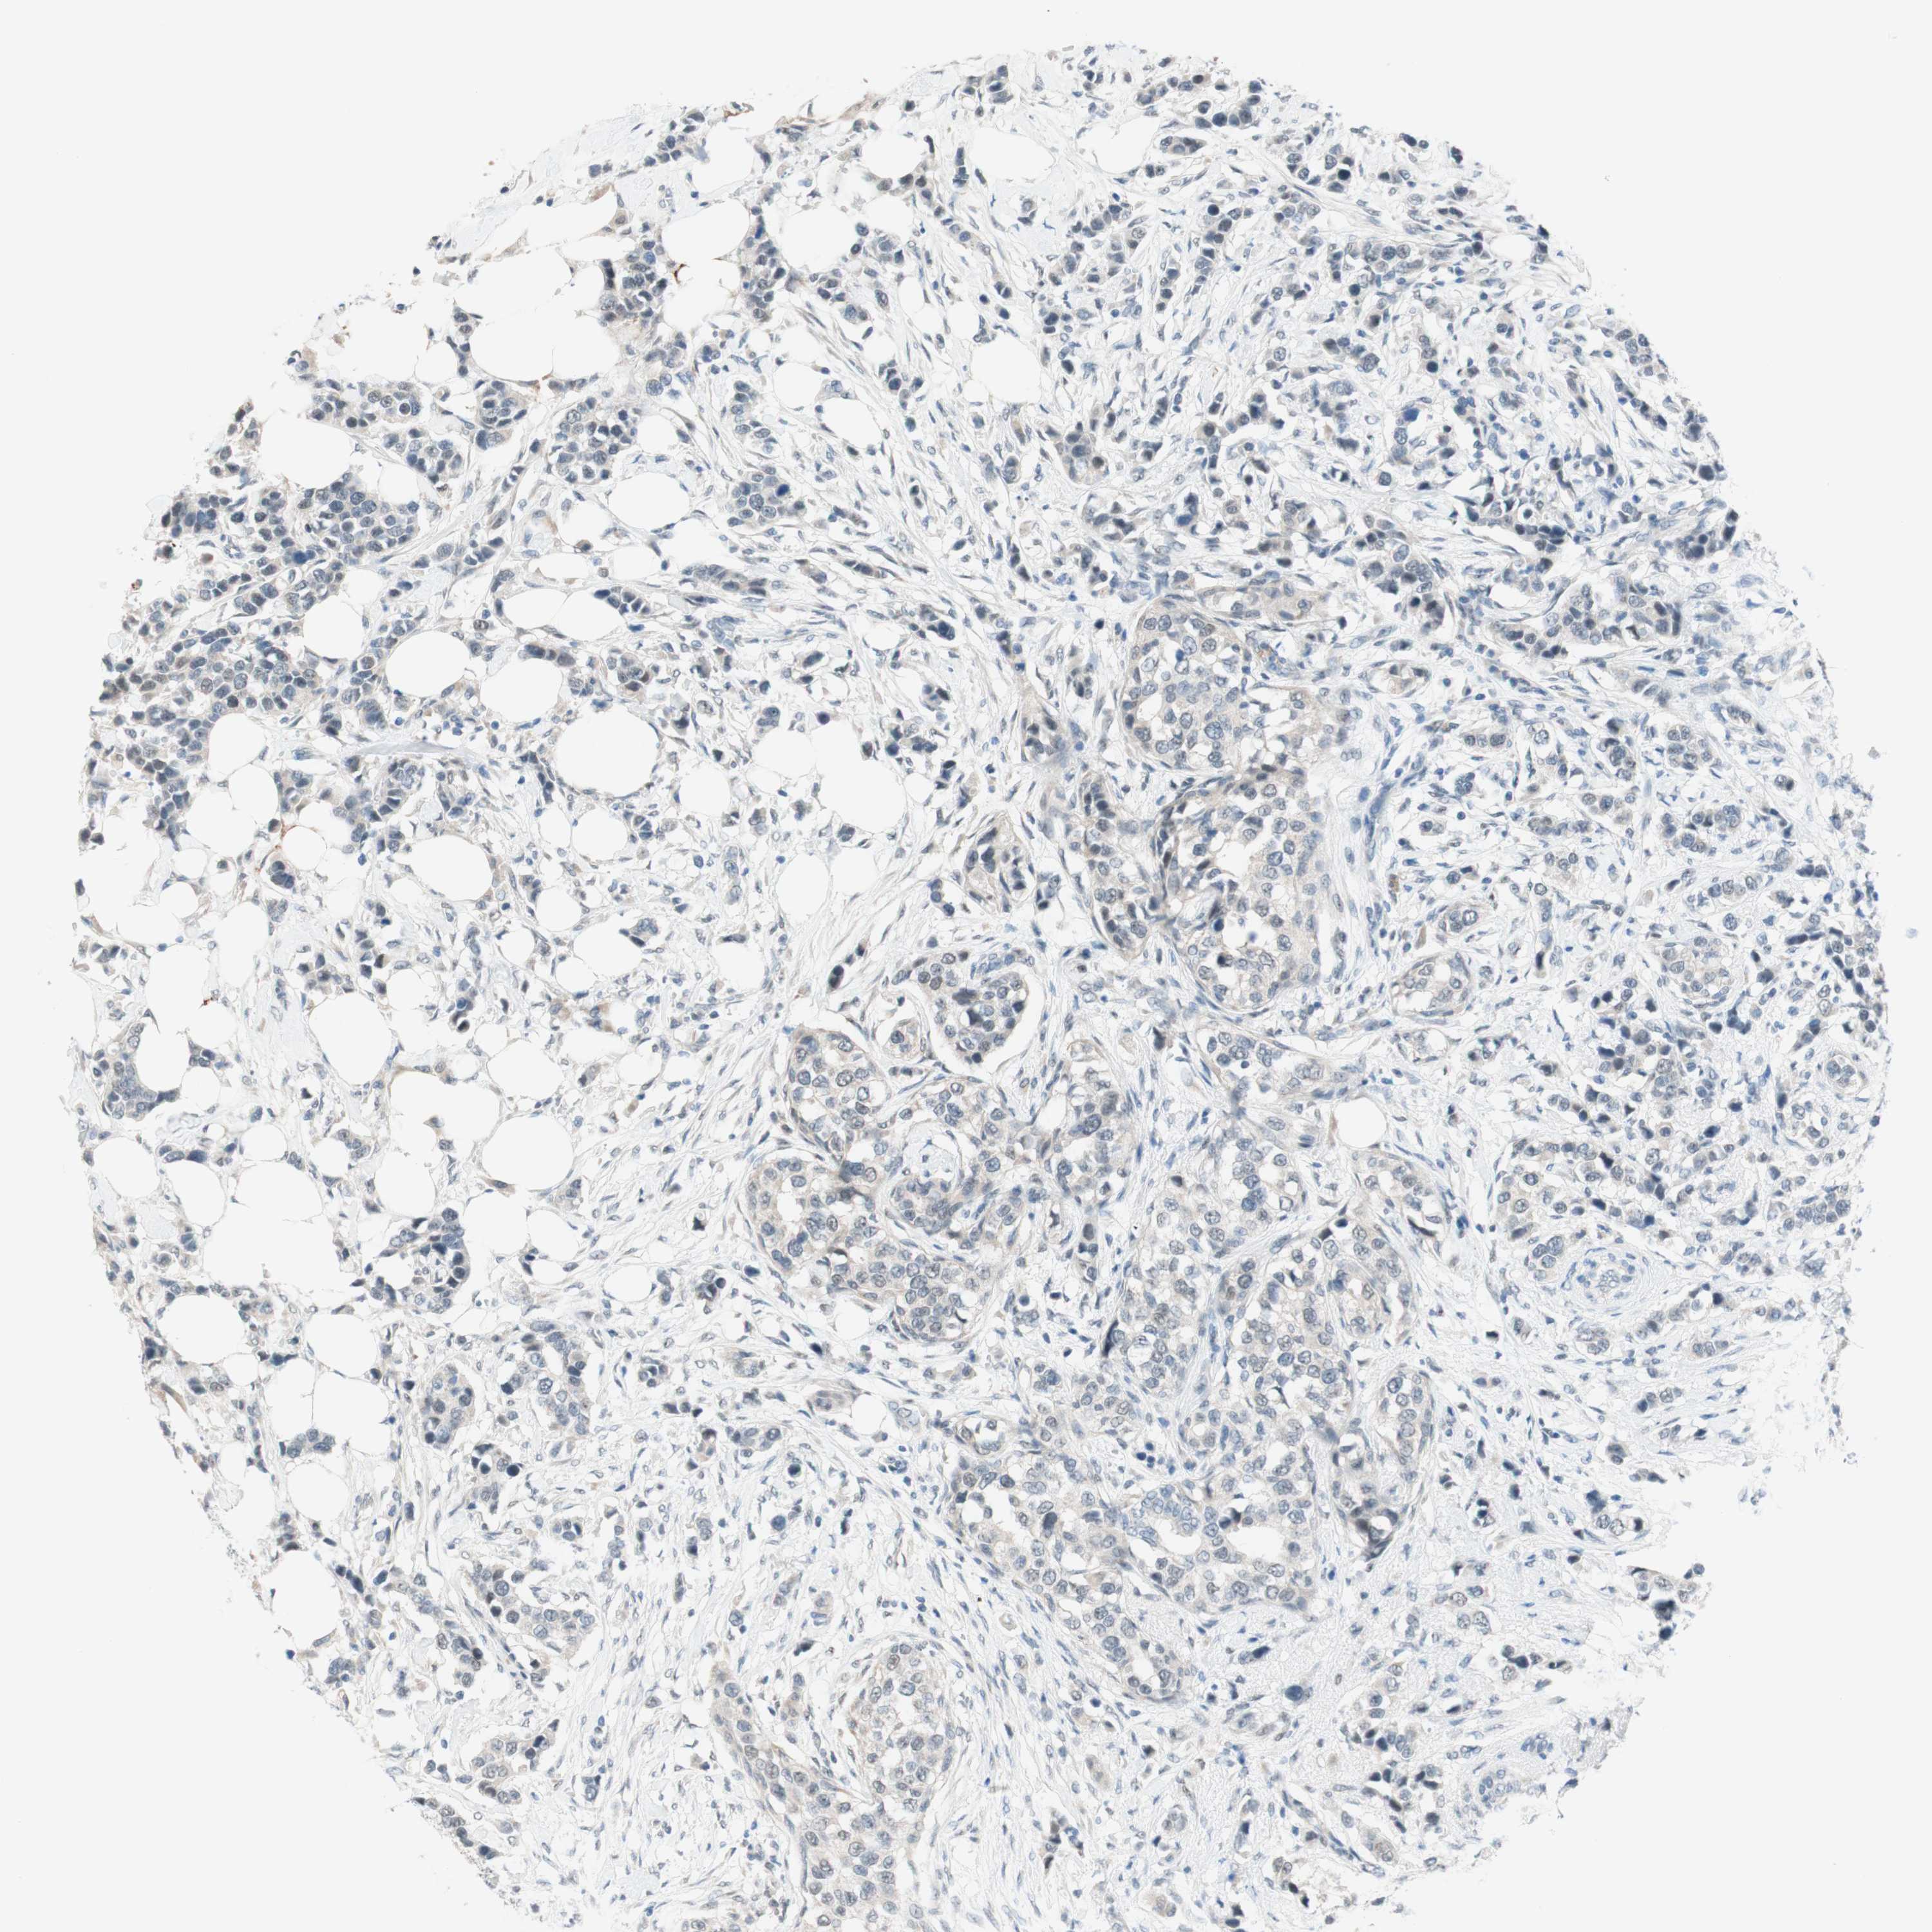

CANCER BREAST CANCER Show tissue menu

BRCA TCGA BRCA VALIDATION PROTEIN EXPRESSION